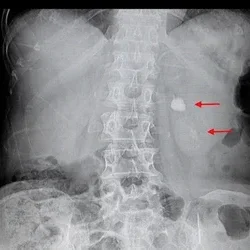

X-ray (KUB) for tracking stone movement

Ultrasound or CT scan to locate and measure the stones